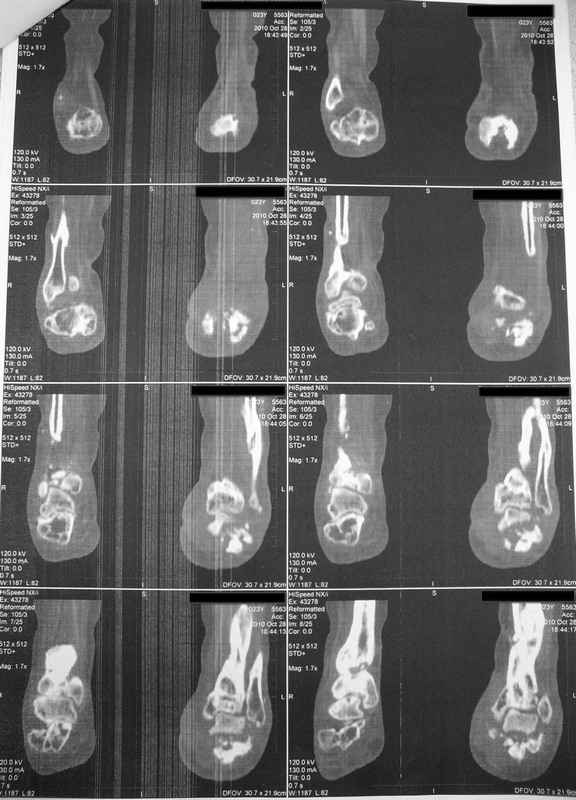

Молодая девушка со сросшимися многооскольчатыми переломами пяток и голеней.Young girl

with fractures of the calcaneus

Больная Н., 25 лет, падение с высоты (2008 г.). Жалобы на боли в области голеностопных

суставах, в области пяток при ходьбе. Лечилась в аппаратах внешней фиксации по поводу

открытых оскольчатых переломов обеих голеней, переломов пяток. Далее по поводу

несросшихся переломов голеней ЧКОС аппаратами внешней фиксации. Переломы срослись,

аппараты демонтированы весной 2010г. В левой пяточной области в месте проведения спицы

имеется сукровичное отделяемое. При ревизии гноя нет. Чем помочь девушке?

Patient N., age

25, falls from heights (2008). Complaints of pain in the ankles, in the heel when walking. She

was treated by external fixation on open comminuted fractures of both legs, fractures of the

calcaneus. Then she was treated by external fixation from nonunion of both legs. Now

fractures are fused, apparatuses removed in the spring of 2010. How to help a girl?